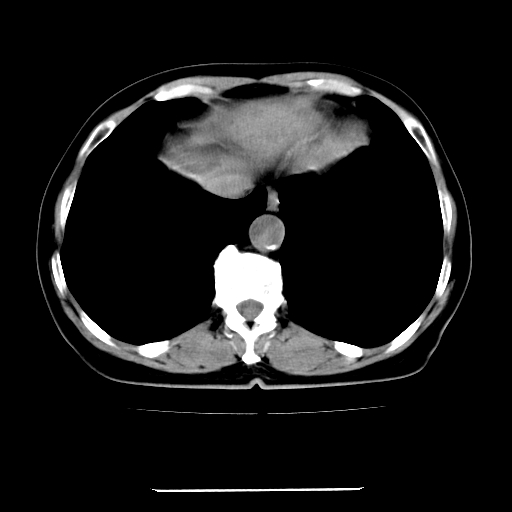

女,67岁,上腹部疼痛一周伴皮肤黄染,无发热。

左叶肝内胆管结石,并远端肝内胆管扩张。

考虑:肝内胆管结石继发肝内胆管扩张,右肾旋转不良。

支持肝内胆管结石并肝内胆管扩张。

肝内外胆管结石并肝内胆管扩张。